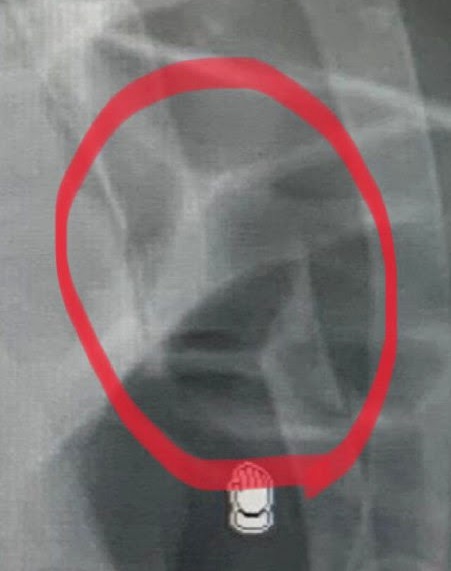

El parte médico aclara que el paciente: “acude refiriendo dolor de hemitorax izquierdo tras evolución posterior a contusión con el toro. No hematoma, dolor a palpación de los arcos costales 9º -10º. Se confirma la fractura cerrada de la costilla 10ª. Doctor: Rodríguez Espinoza.